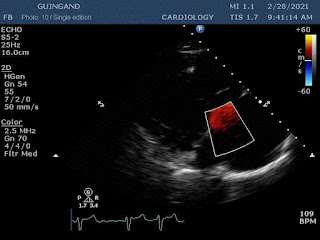

These are the first Cardiology NFTs for sale on a marketplace.

37 unique photos of the artist's most recent echocardiogram.

“Art is inside of us too.”